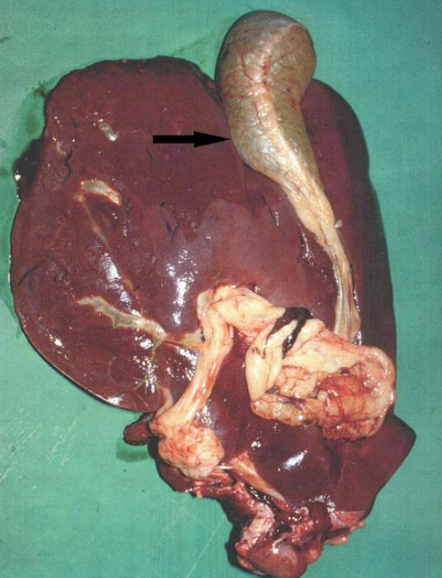

剖檢變化:

1.急性病例

主要是肝臟發(fā)生病變,剖檢發(fā)現(xiàn)有急性肝炎病變,肝臟發(fā)生腫大,肝包膜上沉積有纖維物質(zhì),肝實(shí)質(zhì)內(nèi)存在暗紅色蟲(chóng)道,且蟲(chóng)道內(nèi)存在幼蟲(chóng)和凝固血液。

2.慢性病例

主要是肝臟和膽管發(fā)生病變,剖檢發(fā)現(xiàn)有慢性增生性肝炎,肝實(shí)質(zhì)萎縮,邊緣鈍圓,質(zhì)地變硬,小葉間結(jié)締組織明顯增生;發(fā)生膽管炎,膽管變得肥厚,膽管內(nèi)存在棕紅色蟲(chóng)體。